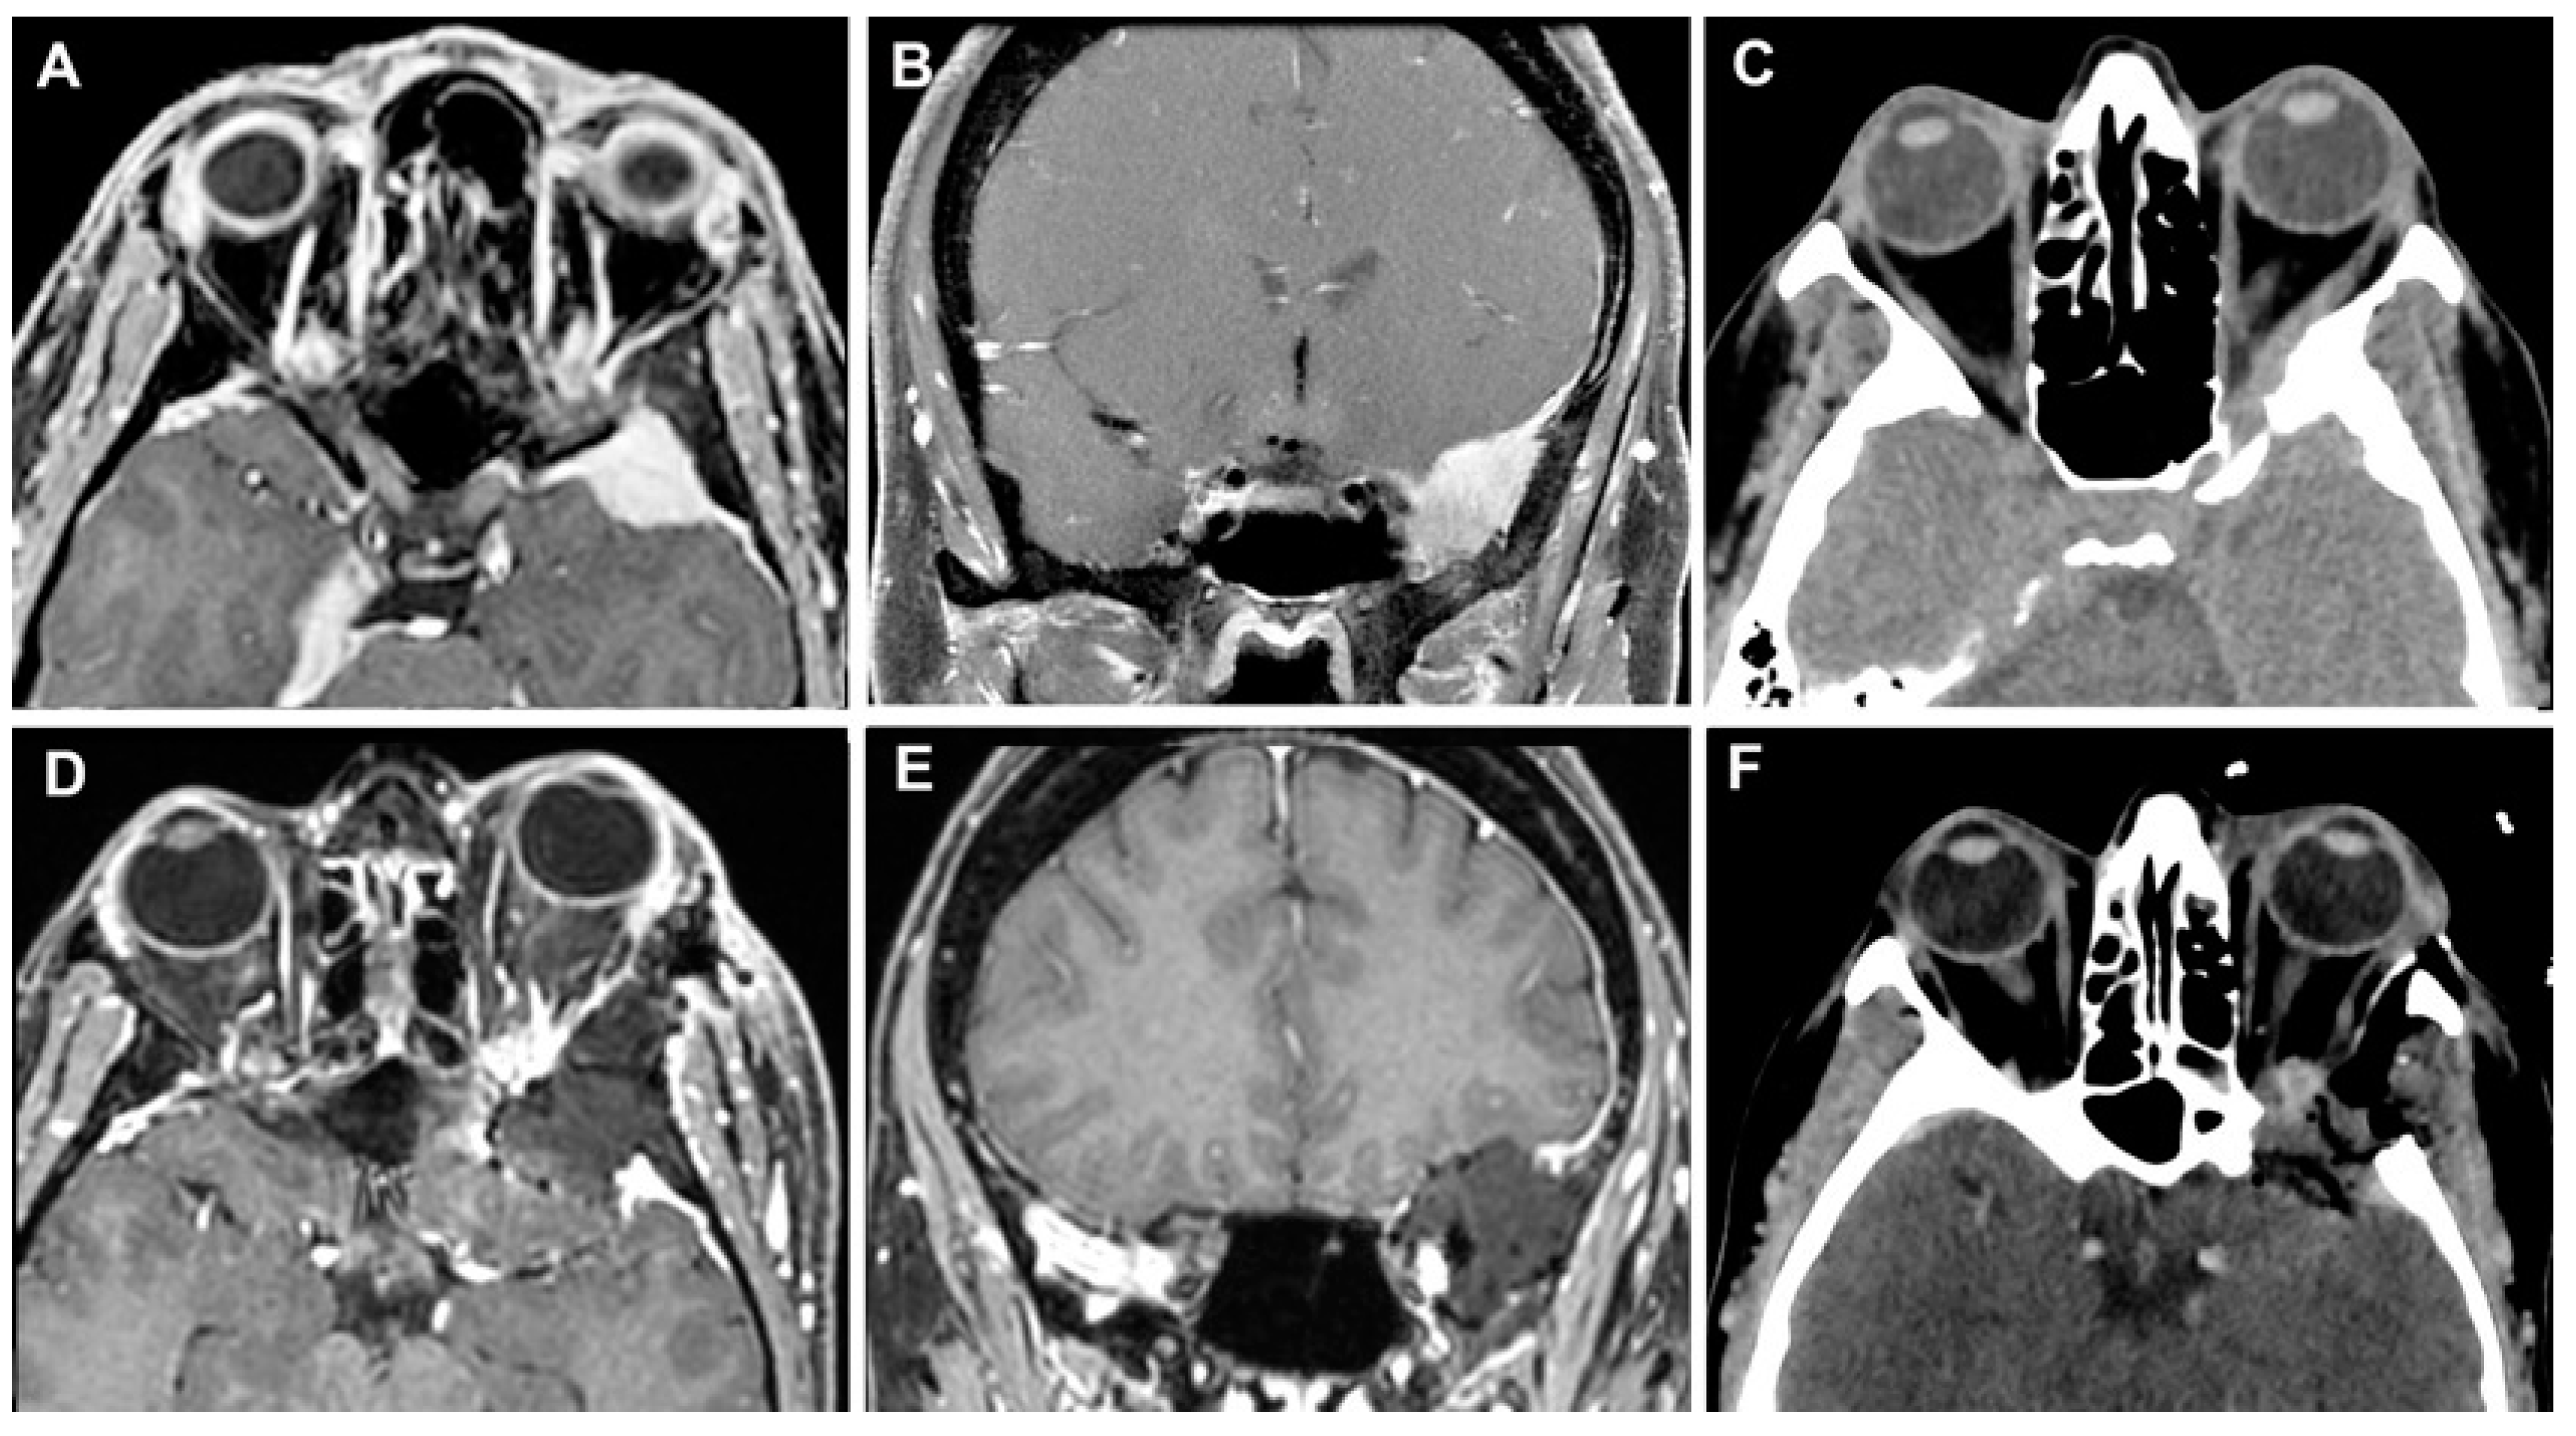

3.3.3. Case 3